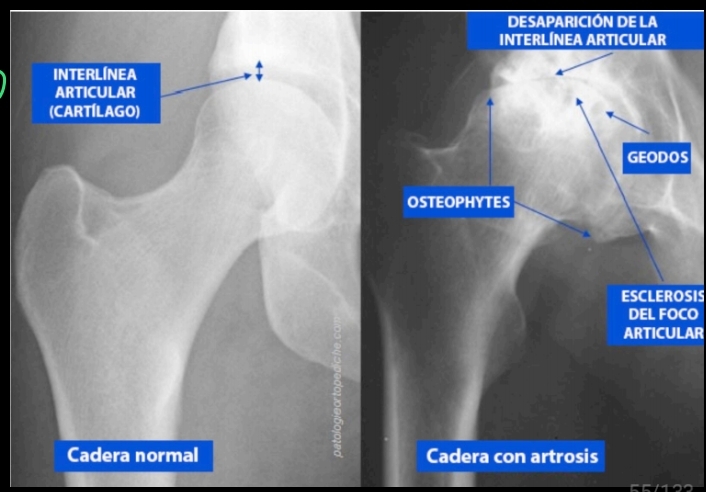

Método diagnóstico más accesible de la coxartrosis

A

Rx

Orden de presentación de la osteoartrosis

1. Osteofitos

2. Disminución del espacio articular

3. Esclerosis osea (mayor opacidad)

4. Quistes subcondrales “geodas”

5. Deformidad osea

8

Q

V/F

En la TC se pueden apreciar los mismos datos de una coxartrosis que en una Rx?

Verdadero

- Osteofitos

- Disminución del espacio articular

- Esclerosis osea

- Quistes subcondrales

- deformidad osea